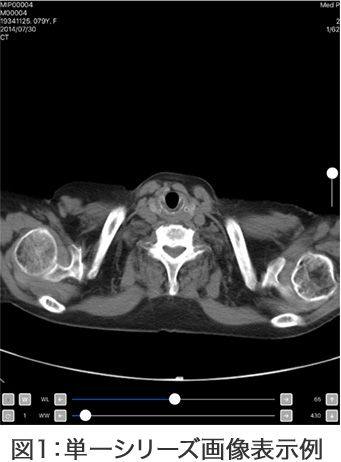

画像参照のUIツール:図1

- 画像の拡大・縮小

- WL/WWの変更

- アノテーション表示

- 画像の移動